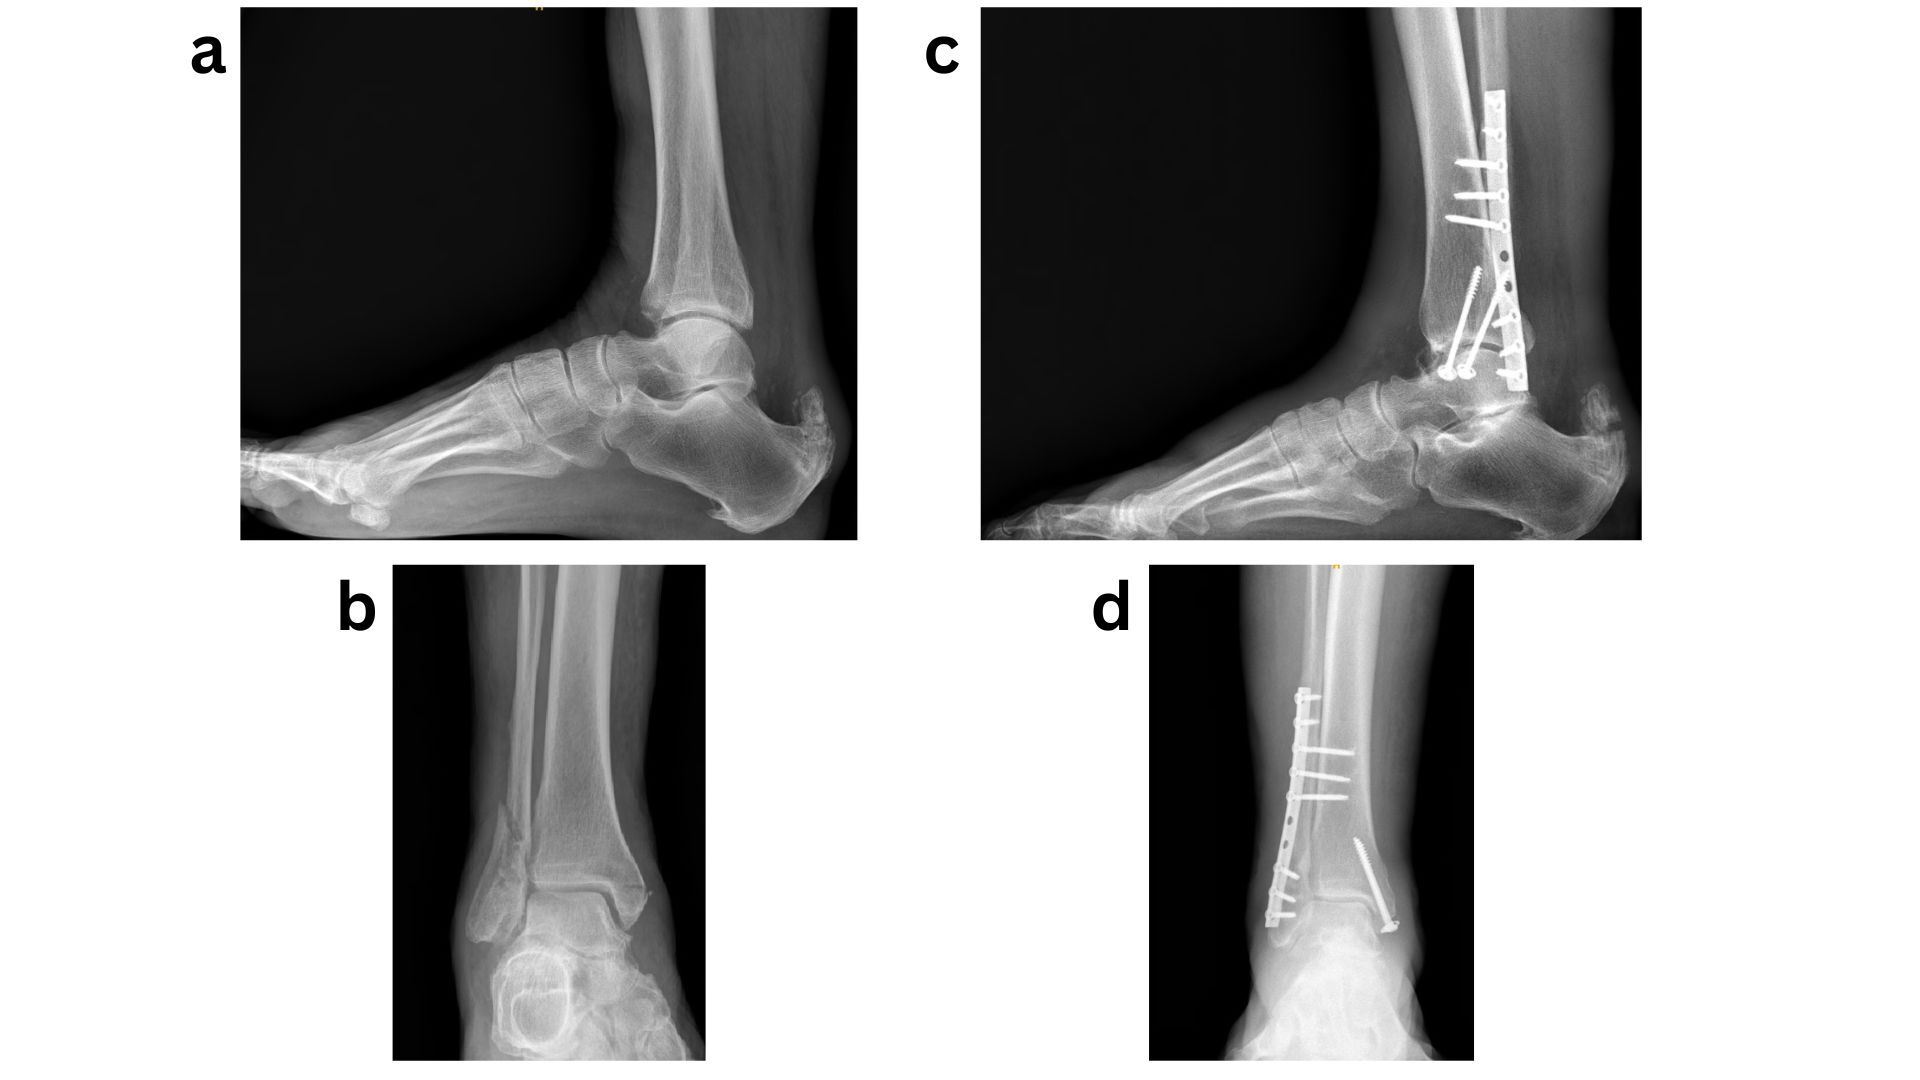

For more complex cases, particularly in the setting of complicated diabetes especially severe neuropathy, BOFAS recommends primary arthrodesis using tibio-talo-calcaneal (TTC) nailing as a limb-salvage strategy (Fig 3). Ebaugh et al. reported high limb salvage rates following primary TTC arthrodesis with retrograde hindfoot nails, with most patients maintaining ambulatory function despite a moderate complication rate. The ability to allow earlier weight-bearing with retrograde hindfoot nails, compared with prolonged immobilisation required by other fixation methods, likely contributed to favourable union rates and reduced certain complications. This approach should therefore be strongly considered in complex or limb-threatening presentations.41

Overall, there is no uniform treatment strategy for diabetic ankle fractures. Optimal management requires an individualized approach that accounts for fracture pattern, injury severity, soft-tissue condition, and patient-specific factors, particularly the presence and extent of complicated diabetes (Fig 4).